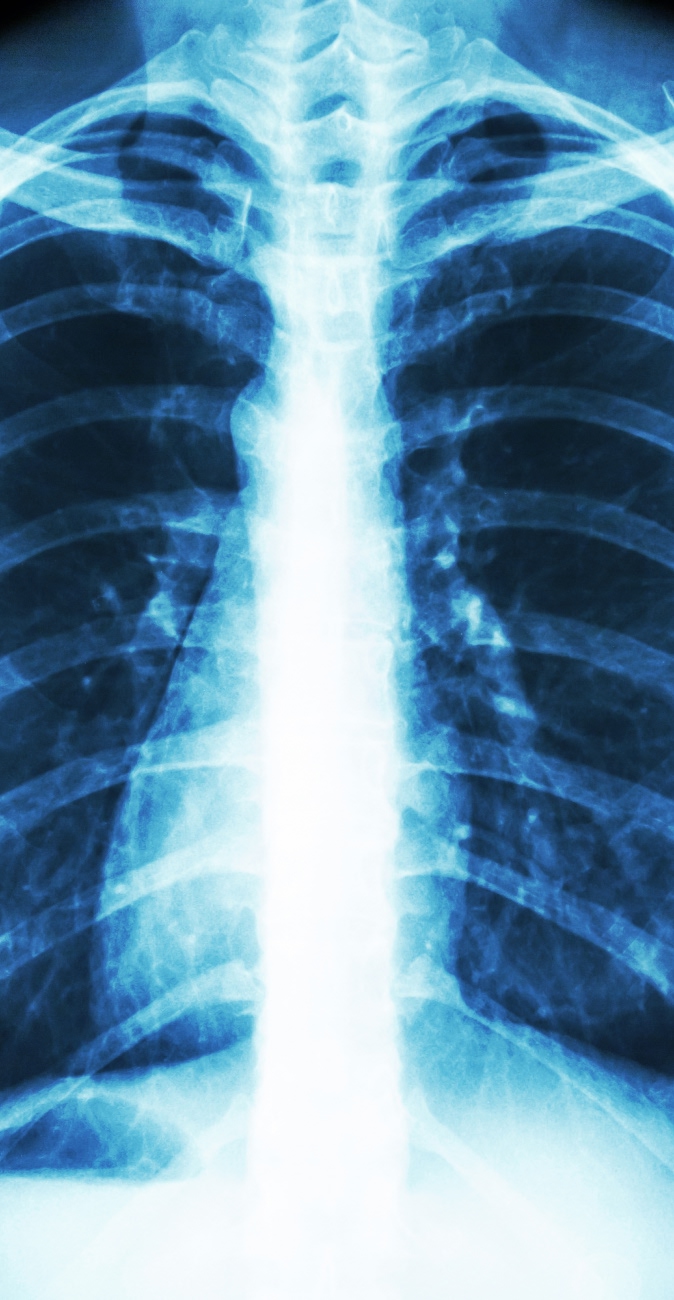

La mayor parte de la morbilidad y la mortalidad debidas a traumatismos torácicos se deben a que las lesiones interfieren con la respiración, la circulación o ambas.

Las lesiones que dañan directamente el pulmón o las vías respiratorias incluyen contusión pulmonar y rotura traqueobronquial. Las lesiones que alteran la mecánica de la respiración incluyen hemotórax , neumotórax y tórax inestable . La lesión del pulmón, el árbol traqueobronquial o, en raras ocasiones, el esófago puede permitir que entre aire en los tejidos blandos del tórax y / o el cuello (enfisema subcutáneo) o mediastino ( neumomediastino ). Este aire en sí mismo rara vez tiene consecuencias fisiológicas importantes; la lesión subyacente es el problema. El neumotórax a tensión altera la respiración y la circulación.

El sangrado, como ocurre en el hemotórax, puede ser masivo y causar shock (la respiración también se altera si el hemotórax es grande). La disminución del retorno venoso altera el llenado cardíaco y provoca hipotensión. La disminución del retorno venoso puede ocurrir debido al aumento de la presión intratorácica en el neumotórax a tensión o al aumento de la presión intrapericárdica en el taponamiento cardíaco . La insuficiencia cardíaca y / o anomalías en la conducción pueden ser el resultado de una lesión cardíaca cerrada que daña el miocardio o las válvulas cardíacas.

Debido a que las lesiones de la pared torácica suelen hacer que la respiración sea muy dolorosa, los pacientes a menudo limitan la inspiración (entablillado). Una complicación común de la ferulización es la atelectasia , que puede provocar hipoxemia, neumonía o ambas.